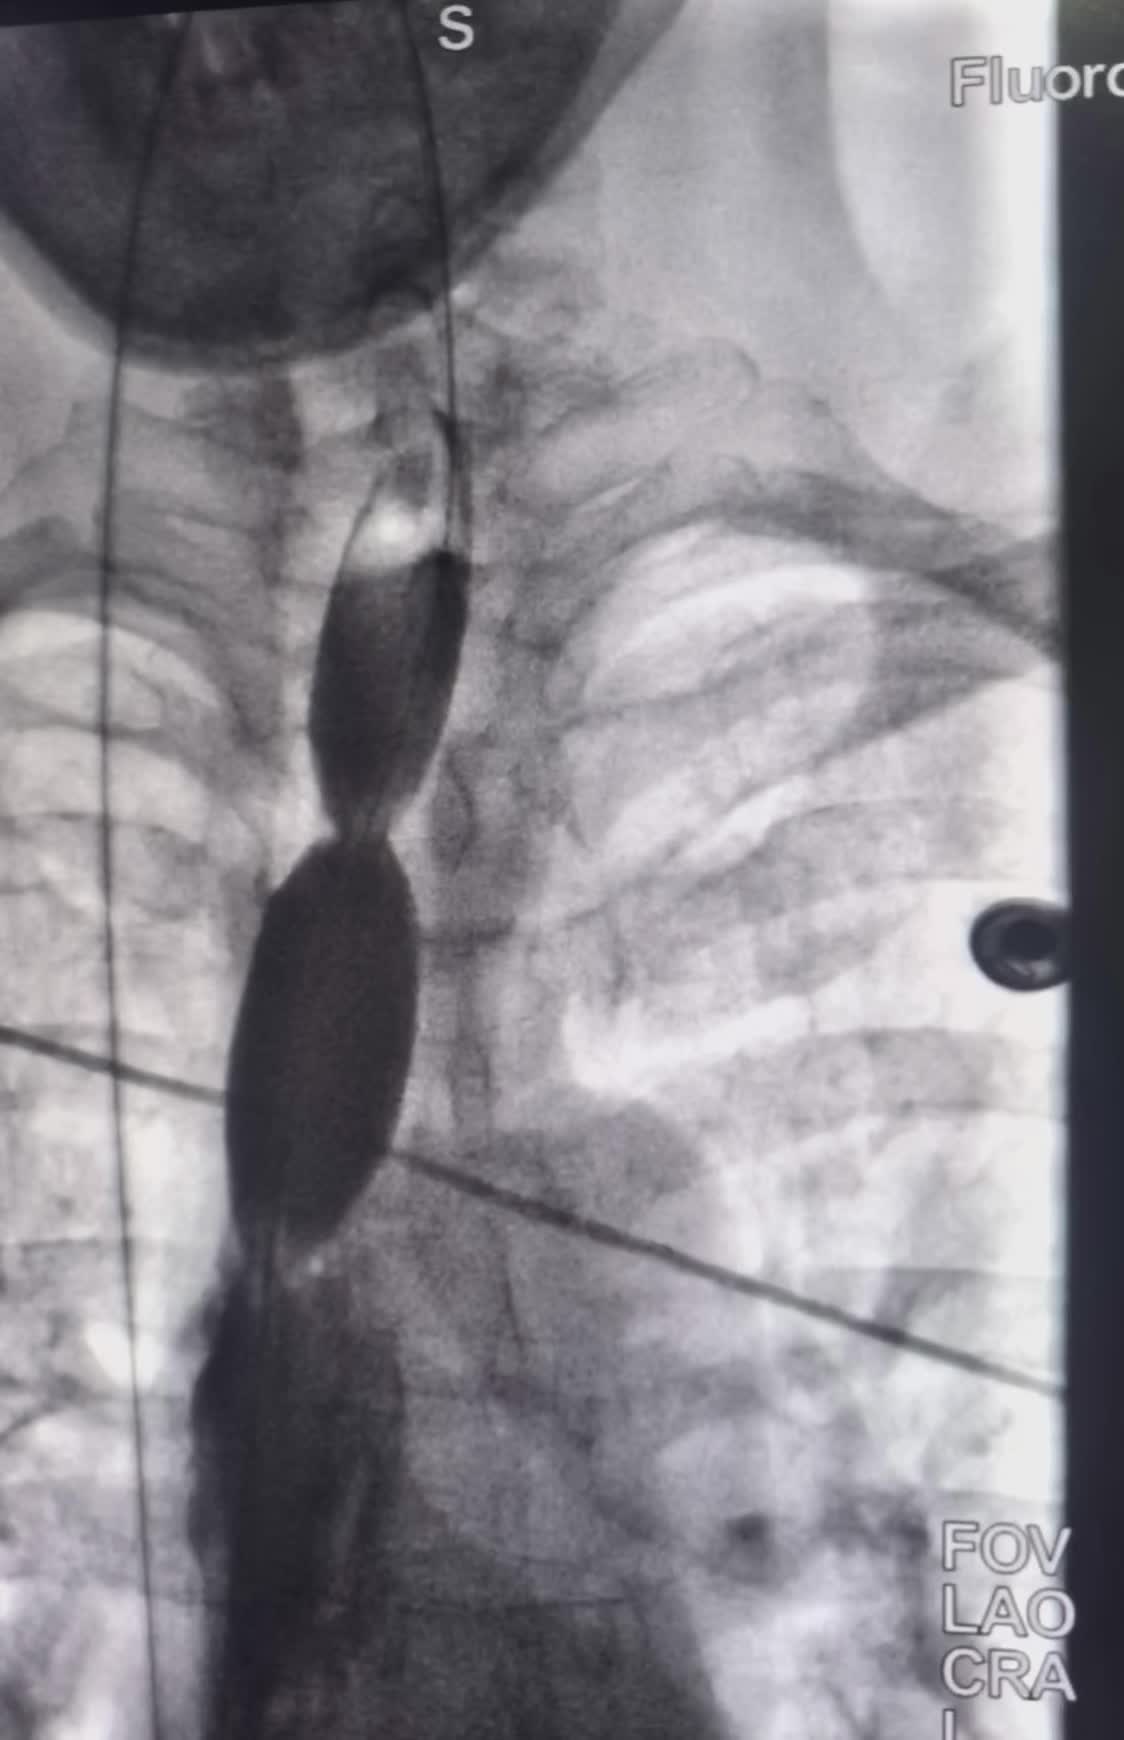

上午一台食管癌术后吻合口狭窄球囊扩张成型 上午一台食管癌术后吻合口狭窄球囊扩张成型术。术后即可恢复正常饮食。